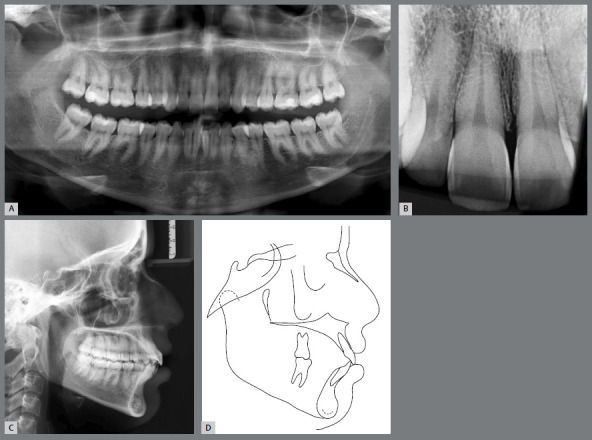

Objective: To describe the treatment of a 23-year-old woman with an Angle Class II, division 1 malocclusion with constricted maxillary and mandibular arches.

Case report: The patient's main complaint was mandibular anterior crowding. The treatment plan included expansion of the mandibular arch concurrent with maxillary expansion, using a MARPE appliance in combination with a full-fixed appliance to align and level the crowded mandibular teeth, along with miniscrews as anchorage for the maxillary teeth and for distalization of the molars and premolars. A successful non-extraction orthodontic treatment was accomplished after 28 months, and the occlusion and teeth alignment, as well as facial goals, were resolved in a clinically satisfactory manner.